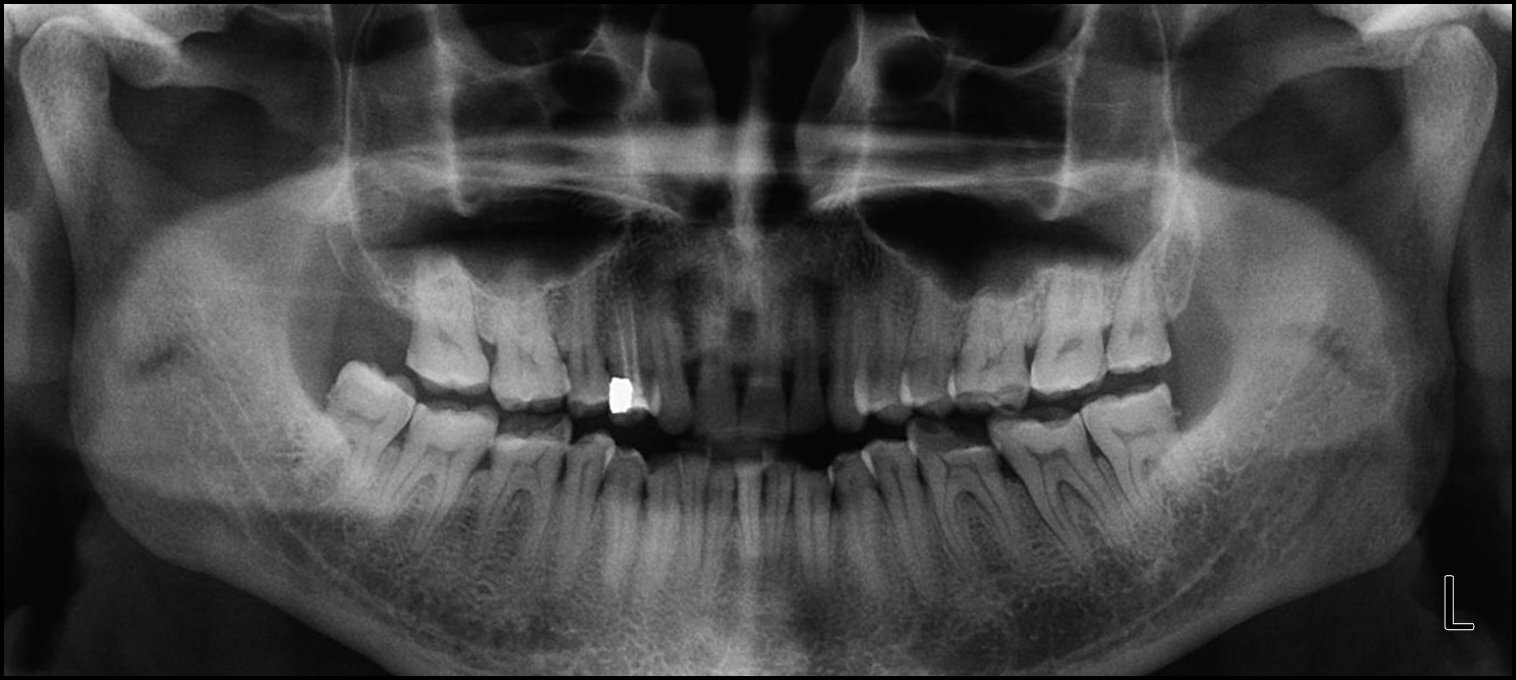

Thirty-six patients (24 F, 12 M) met the inclusion criteria from patients referred to a Prosthodontic dental office for a digital occlusion and muscle physiology evaluation, with a chief complaint of chronic bruxism. In addition to experiencing bruxing habits, many of the referred patients demonstrated chewing fatigue, chewing pain, or chewing weakness, and some experienced ongoing head, neck and facial pain, headaches around the eyes, midface and temples, and frequently noticed jaw tension, Many wore splints that were unsuccessful in arresting their bruxing frequency, but that did act to protect tooth structure from bruxing damage. All of these patients had anterior teeth that coupled or nearly coupled, presented with some worn teeth and exposed dentin, but demonstrated relatively normal occlusal relations. (Figures 1a and 1b) A further examination with Joint Vibration Analysis (JVA), radiography and patient consultation determined that these bruxing patients primarily exhibited muscular TMD symptoms, with complaints related to their tooth structure loss, but who did not present with substantial structural breakdown of their Temporomandibular Joints, discs, or condyles. (Figure 1c)

The pre-treatment T-Scan/BioEMG recordings (Figures 2a and 2b) guided the clinician to the areas to adjust in the ink patterns on the occlusal surfaces as the patient moved in and out of MIP excursively. Definitive corrections were made on one side of the mouth using pear-shaped finishing burs (Mani Dia-Burs, Japan ISO no-237/021), to the excursive frictional contacts located on inclined planes and on inner/outer aspects of the molar and premolar buccal cusps (Figure 3a), leaving the central fossa, cusp tip, and the marginal ridge contact points intact (Figure 3b). These same molar and premolar excursive contacts were then eliminated on all involved surfaces on the opposite side of the mouth. In patients with excessive exposed dentin (Figure 1b), adjustments were concentrated on teeth with the most enamel, or on opposing teeth to those that were markedly worn. And when needed, some minor bonding was added to increase steepness to any shallow maxillary anterior guidance discluding surfaces.